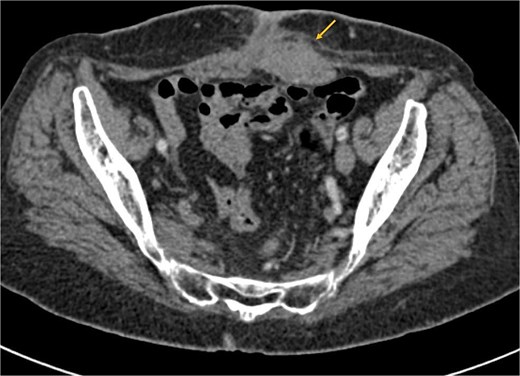

The patient received six cycles of Paclitaxel and Carboplatin, with a good clinical and radiological response (Figs 3 and 4). A follow-up computed tomography (CT) scan after the 3rd cycle of chemotherapy showed a significant reduction in tumor size, measuring 66 × 50 × 30 mm compared to 86 × 59 × 75 mm (Fig. 4).

Axial CT scan showing a significant reduction in the size of the mass post-chemotherapy, now confined to the left rectus abdominis muscle with fat infiltration.